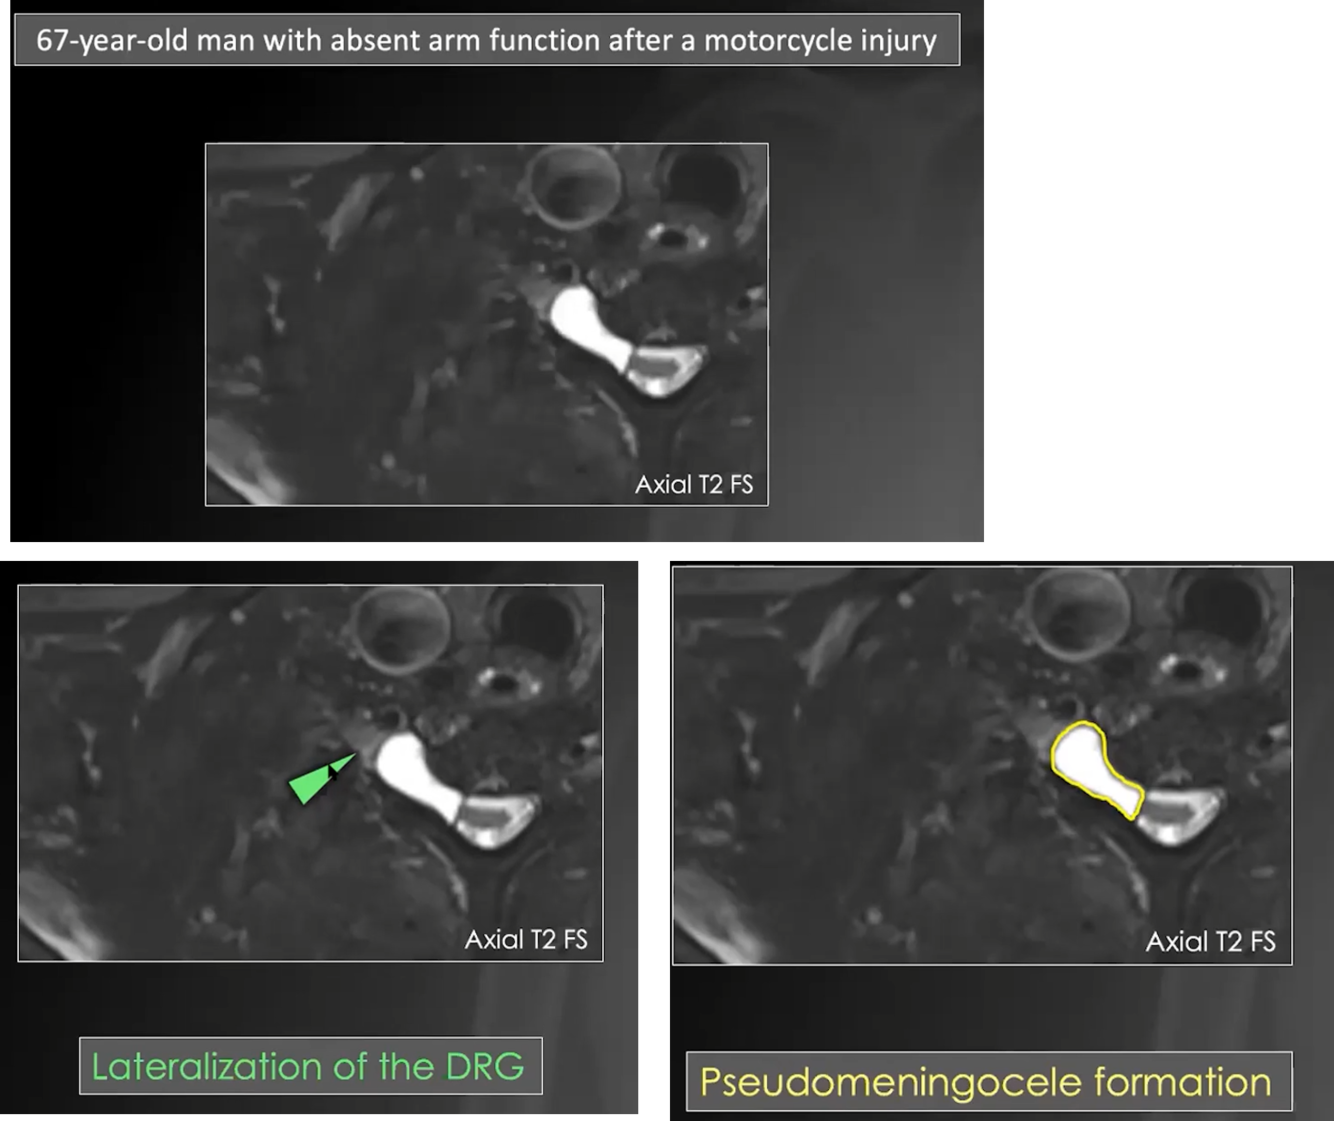

Preganglionic injury

preganglionic injury. discontinuity/absent rootlets, medial to dorsal root ganglion